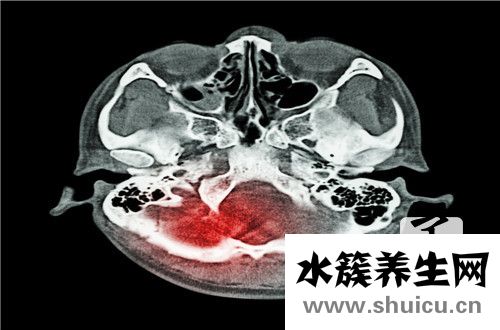

顱骨是保護(hù)人體頭部各種組織和器官的重要骨組織,所以我們?cè)谏钪幸矐?yīng)該注意保護(hù)顱骨,避免頭部顱骨骨折的問(wèn)題。因?yàn)橐坏┦褂昧祟^顱骨骨折,就會(huì)極大地影響一個(gè)人的頭部,從而影響一個(gè)人全身系統(tǒng)的正常...